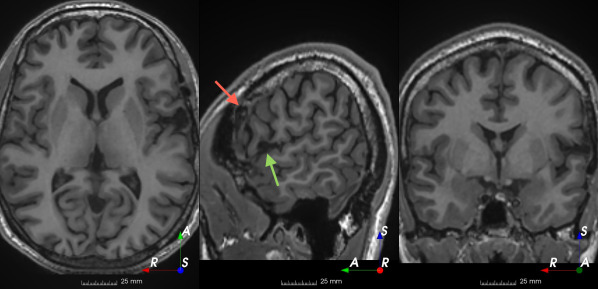

Refer to caption

(a)

(b)

(c)

(d)

(e)

(f)

Figure 3: Manual labels from Rater A (green) and Rater D, the model trained with PubFull + EpiPre + Pseudo (magenta). Errors caused by a (a) small resection, (b) blood clot in cavity and (c) brain shift; segmentations corresponding to the (d) 50th, (e) 75th and (f) 100th percentiles giving a DSC of 81.7, 86.5 and 93.8, respectively.

We trained a model using PubFull, EpiPre and Pseudo (2371 images), obtaining a DSC of 81.7 (14.2). Adding the pseudo-labels to PubFull and EpiPre did not significantly improve performance (p=0.176𝑝0.176p=0.176), indicating our semi-supervised learning approach provided no advantage. Predictions from this model are shown in Fig. 3.

Predictions errors are mostly due to 1) resection of size comparable to sulci (Fig. 6a), 2) unanticipated intensities, such as those caused by the presence of blood clots in the cavity (Fig. 6b), 3) brain shift (Fig. 6c) and 4) white matter hypointensities (Fig. 6e). Further work will involve using different internal and external cavity textures, carefully sampling the resection volume, simulating brain shift using biomechanical models, and quantifying epistemic and aleatoric segmentation uncertainty to better assess model performance [24].